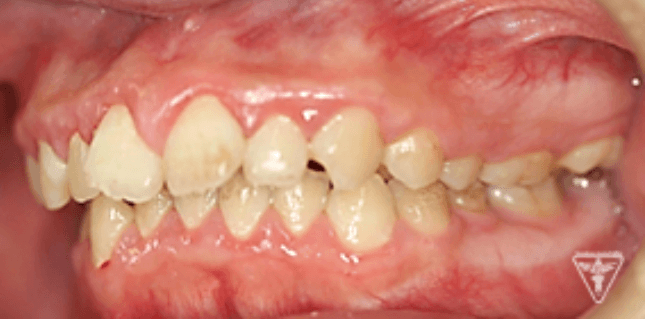

治療前